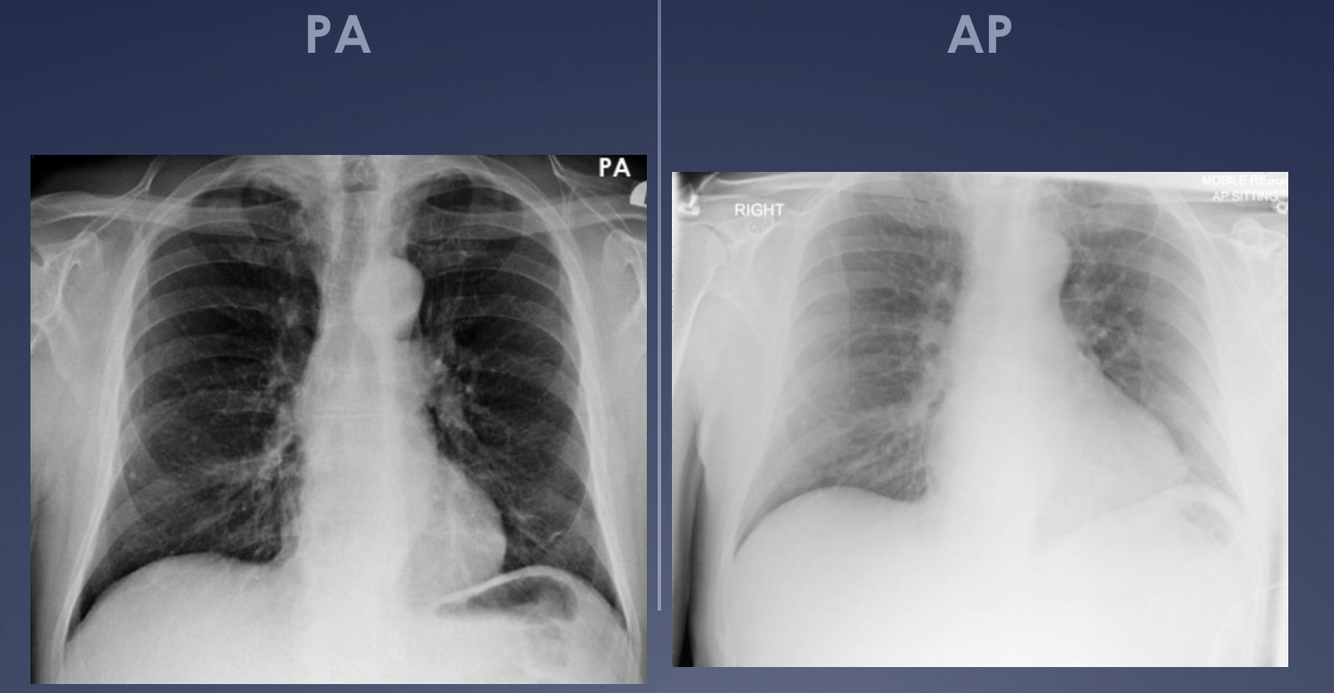

What is the normal projection of chest x-rays?